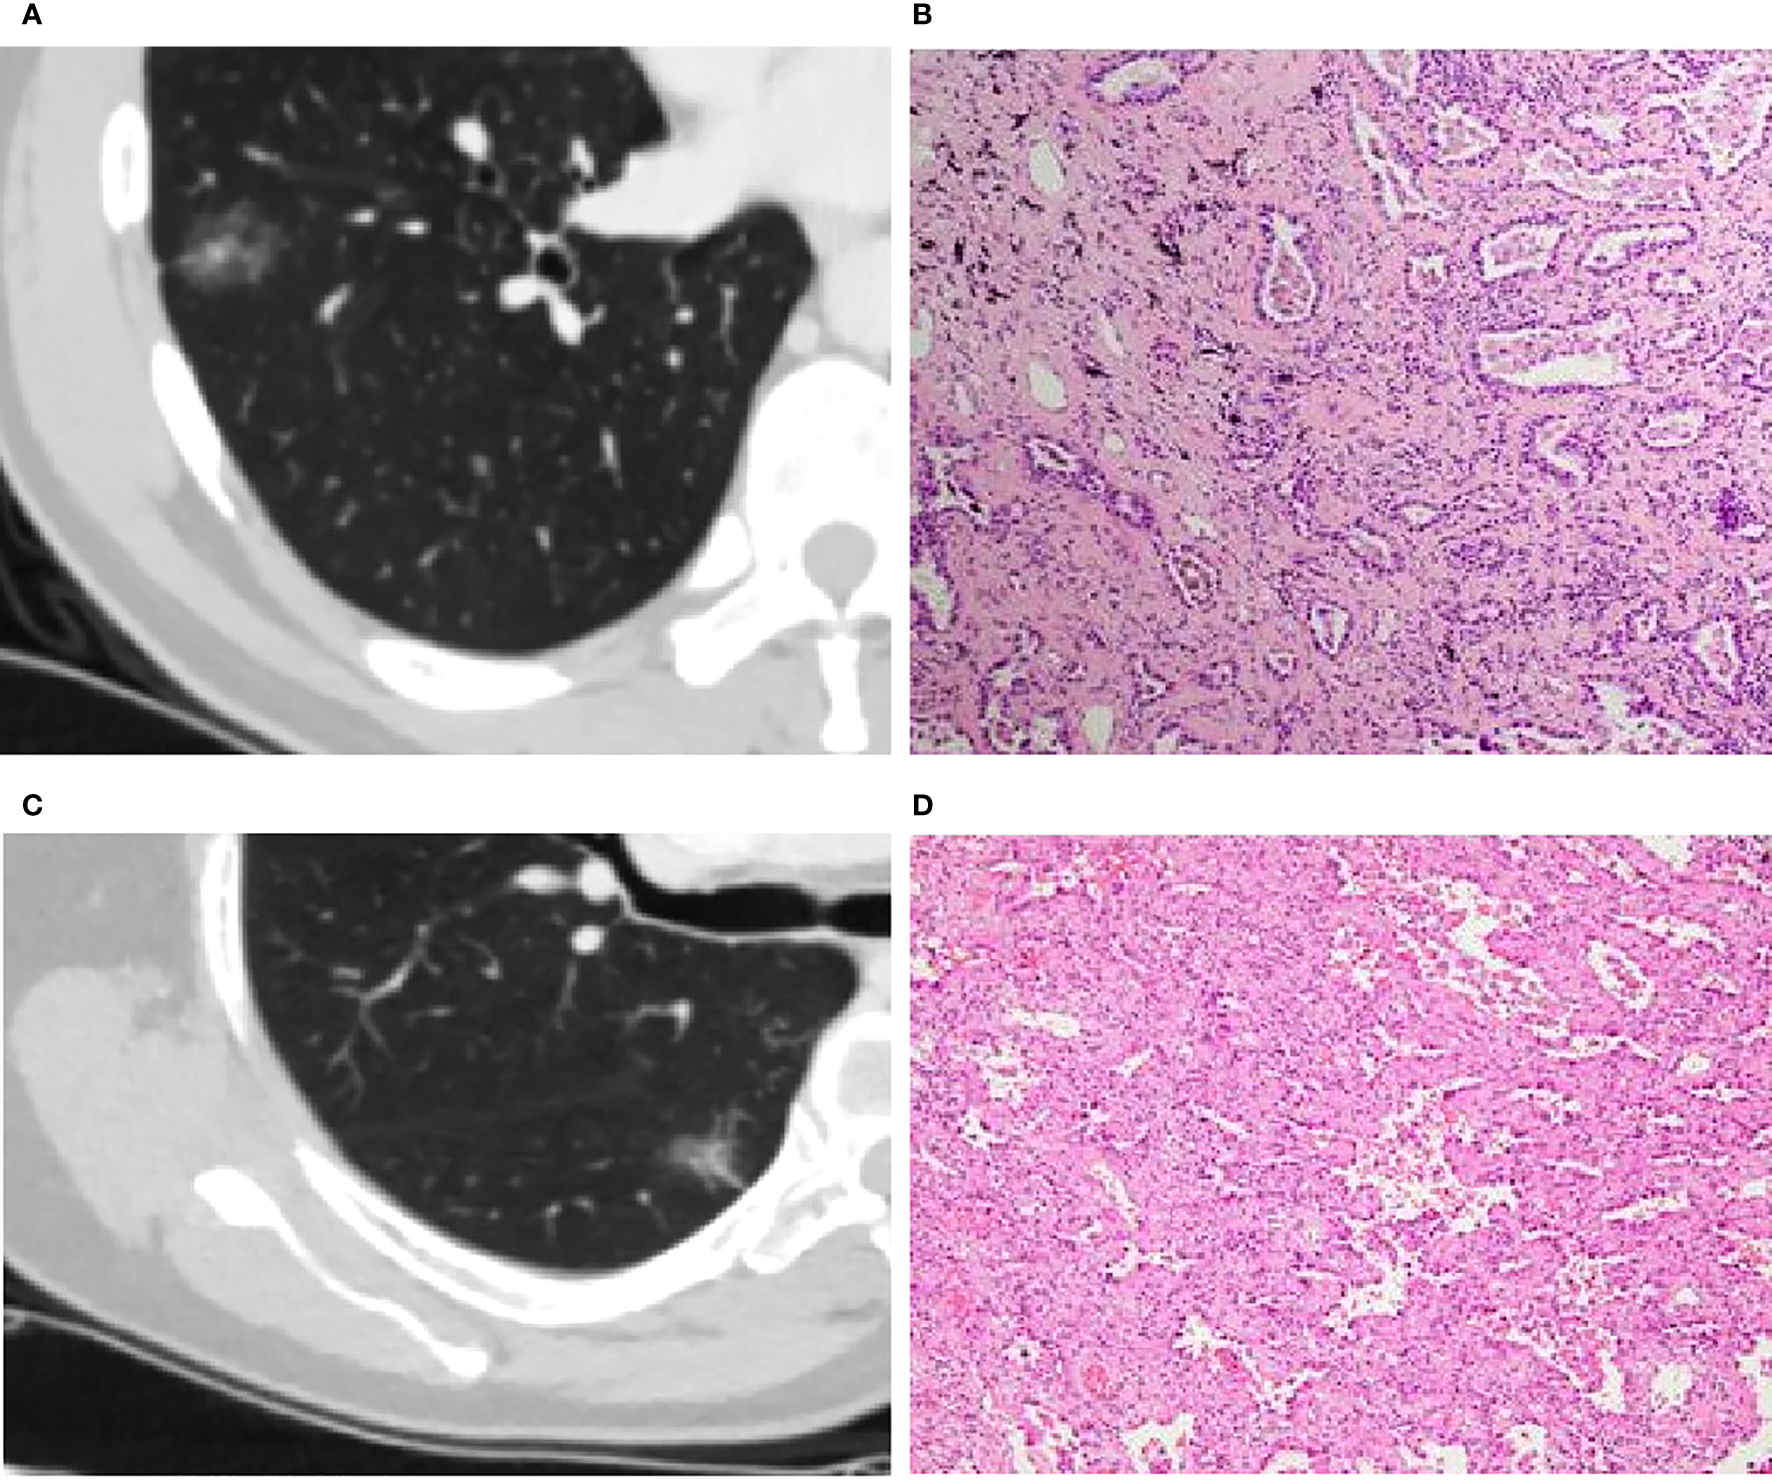

Figure 3

(A, B): Invasive adenocarcinoma (IA) in a 44-year-old man with a part-solid nodule (A). Photomicrograph (H&E staining, ×100) confirmed IA (B). (C, D): Minimal invasive adenocarcinoma (MIA) in a 66-year-old woman with a part-solid nodule (C). Photomicrograph (H&E staining, ×100) confirmed MIA (D).